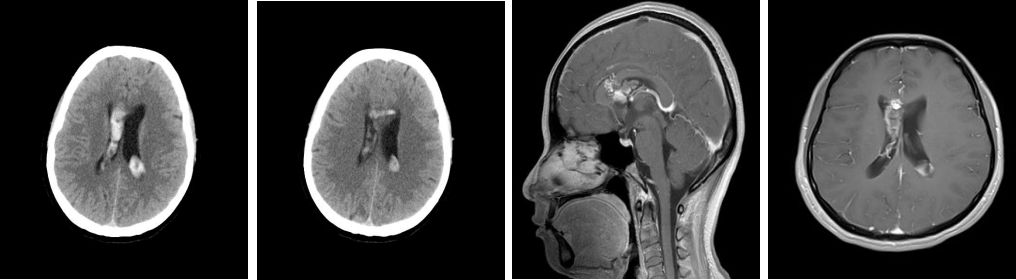

患者女性,39岁,以头痛1月余入院,患者入院前1个月无明显诱因出现头痛、头晕并呕吐,伴有短暂昏迷,当地医院头颅CT、MRI(图1),查体:未见异常。当地医院给予保守治疗,转入我院行DSA(图2)示:右侧胼胝体动静脉畸形。

图1:头颅CT:示脑室出血,头颅MRI:考虑右侧胼胝体动静脉畸形